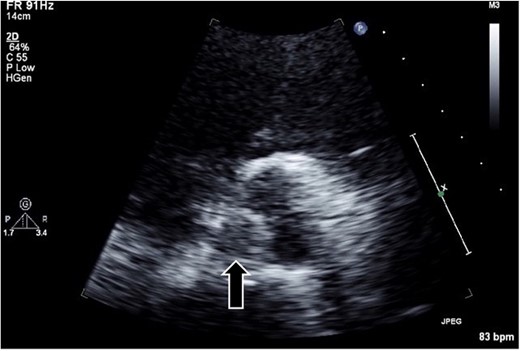

A 54-year-old man presented to our emergency department with shortness of breath on exertion. He had a medical history of hypertension, diabetes, and gastric ulcer. Transthoracic echocardiography (TTE) revealed a low left ventricular ejection fraction (30%). CAG revealed normal left coronary; however, the catheter could not access the abnormally positioned right side. No aortic valve abnormalities or vegetation were observed in TTE or CAG. Seven days post-CAG, TTE revealed a 1-cm vegetation and edematous changes at the noncoronary cusp of the aortic valve (Fig. 1). Laboratory data showed that the cause of thrombus formation was not identified (anticardiolipin IgG, 12.4 APL U/ml; anticardiolipin IgM, 2.9 APL U/ml; protein C, 52%; and protein S, 43%). Brain magnetic resonance imaging revealed multiple acute cerebral infarct lesions. Therefore, the patient underwent urgent thrombectomy.

Transthoracic echocardiography in the parasternal short-axis view revealing a hypo- or iso-echoic mass (arrow; ~1 cm in diameter) on the noncoronary cusp of the aortic valve.